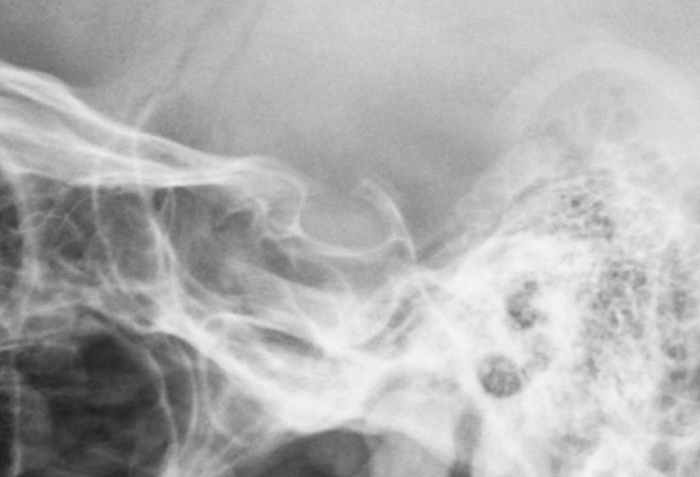

Рентген турецкого седла - важный метод исследования, который позволяет получить детальное изображение области турецкого седла головного мозга.

Показания к проведению рентгена турецкого седла:

• повышение уровня пролактина в крови;

• подозрение на наличие опухолевого поражения гипофиза (по современным рекомендациям показано выполнение МРТ гипофиза с контрастным усилением).